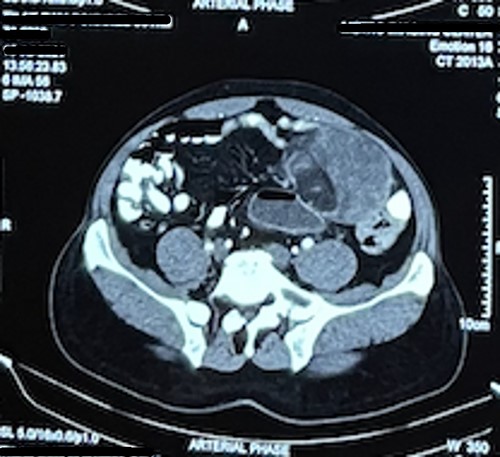

Laboratory test including tumor marker (carcinoembryonic antigen) was normal. Abdominal ultrasonography revealed heteroechoic mass over left iliac fossa with regular borders. Computed tomography (CT) of the abdomen revealed well-defined space-occupying lesion of size 10 × 8.5 × 7 cm at the left iliac fossa. There were no areas of calcification; however, plane between the mass and the bowel was lost in few places suggesting of invasion (Figs 1 and 2).